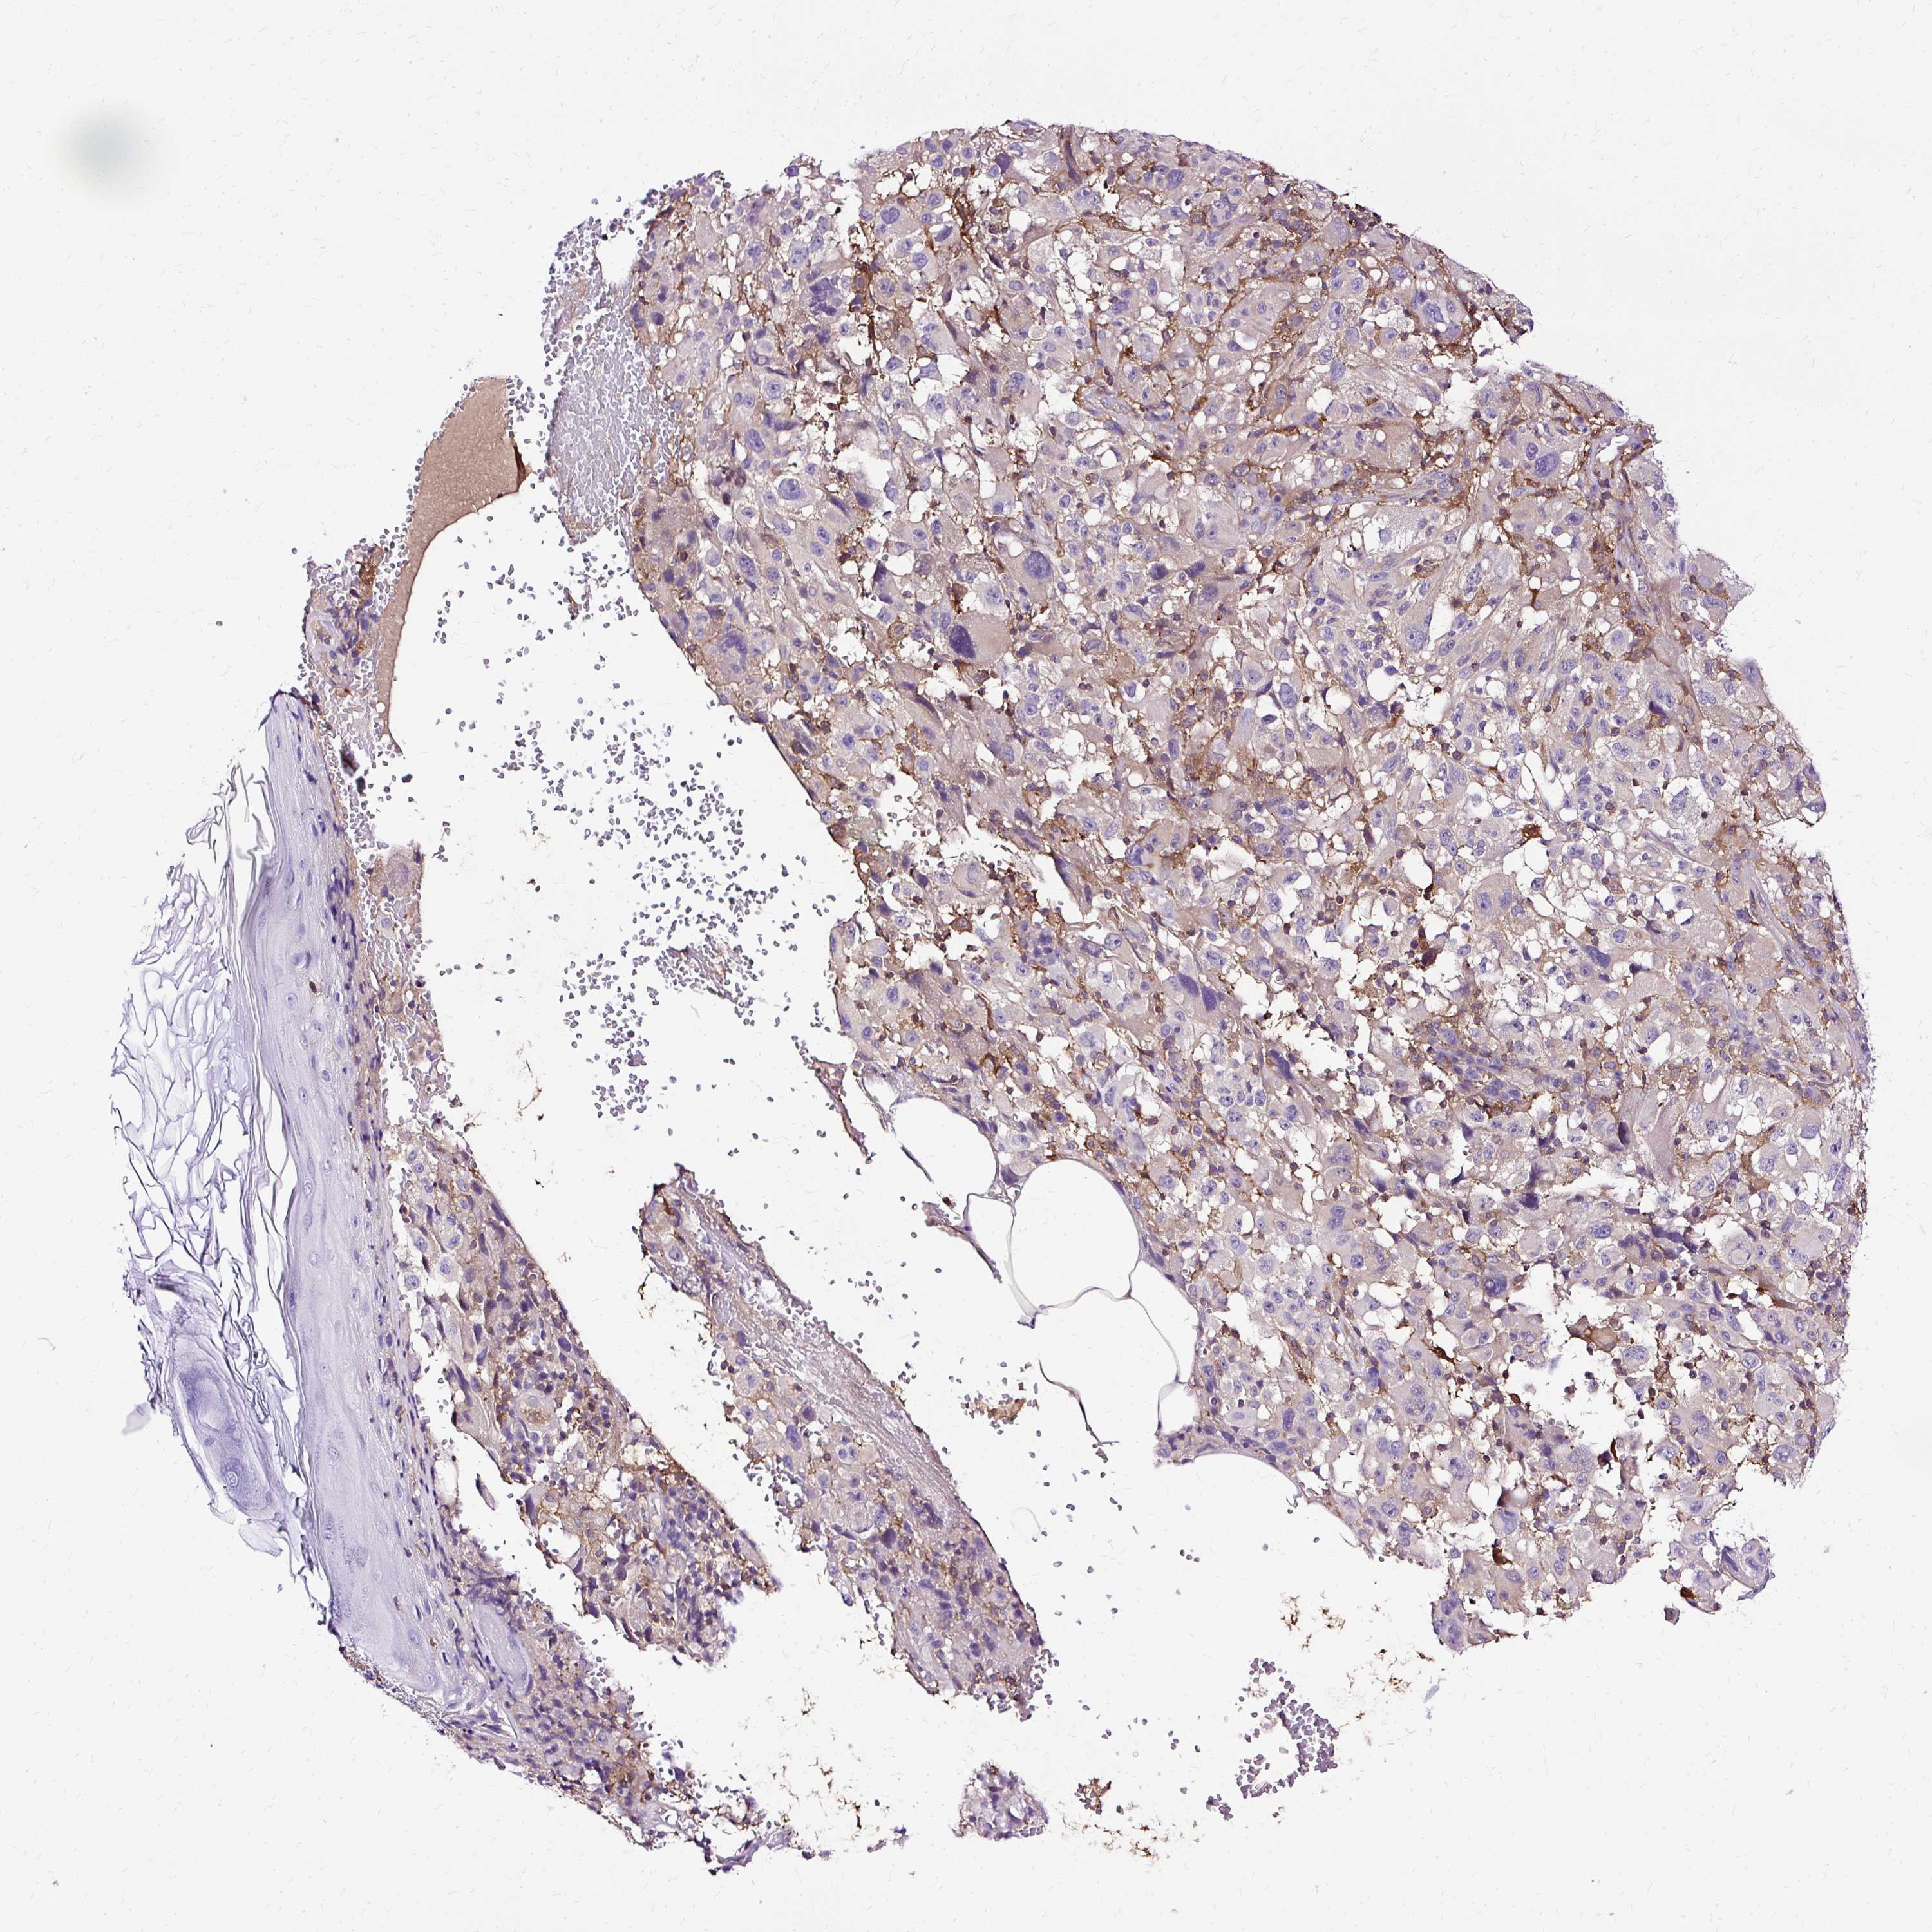

MELANOMA - Protein expressioni

A mouse-over function shows sample information and annotation data. Click on an image to view it in a full screen mode. Samples can be filtered based on level of antibody staining by selecting one or several of the following categories: high, medium, low and not detected. The assay and annotation is described here.

Note that samples used for immunohistochemistry by the Human Protein Atlas do not correspond to samples in the TCGA dataset.

Antibody stainingi

Antibody staining in the annotated cell types in the current human tissue is reported as not detected, low, medium, or high, based on conventional immunohistochemistry profiling in selected tissues. This score is based on the combination of the staining intensity and fraction of stained cells.

Each image is clickable and will lead to virtual microscopy that enables deeper exploration of all samples and also displays staining intensity scores, fraction scores and subcellular localization as well as patient and tissue information for each sample.

Antibody HPA053874

Staining

High

Medium

Low

Not detected

Intensity

Strong

Moderate

Weak

Negative

Quantity

>75%

75%-25%

<25%

None

Location

Nuclear

Cytoplasmic/membranous

Cytoplasmic/membranous,nuclear

Malignant melanoma, NOS

Malignant melanoma, Metastatic site